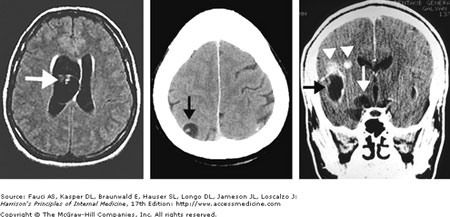

Khi các nang này xuất hiện trong não, các bệnh nhân có thể bị nhức đầu, động kinh, co giật, nôn mửa, liệt bán thân, mất khả năng điều hòa vận động các cơvà vận động các cơ chi. Nhiều triệu chứng trong số này do tăng áp lực nội sọ bởi sự phát triển của các nang chèn vào các phần của não khác nhau.

Vì bệnh lý này hiếm khi xuất hiện trên người, nên việc chẩn đoán chính xác từ lâu chưa phát triển và quan tâm đầu tư. Chụp phim CT scans và MRI có thể có ích trong việc phát hiện các nang chứa đầy dịch tại hầu hết các vùng trong cơ thể và một số thử nghiệm huyết thanh học và hình thái học có thể xác định có mặt của ấu trùng sán Taenia spp. khi phẩu thuật tiến hành và một phần nào đó của nang có thể được loại bỏ và đưa đi sinh thiết và phân tích mô bệnh học.

Vì thiếu độ đặc hiệu các kỹ thuật chẩn đoán, nên bệnh nang sán nhiều đầu có thể bị chẩn đoán nhầm với bệnh lý ấu trùng sán dây lợn thể thần kinh hay bệnh nang sán chó Echinococcus spp, hay các ký sinh trùng khác tác động trên mô thần kinh trung ương.